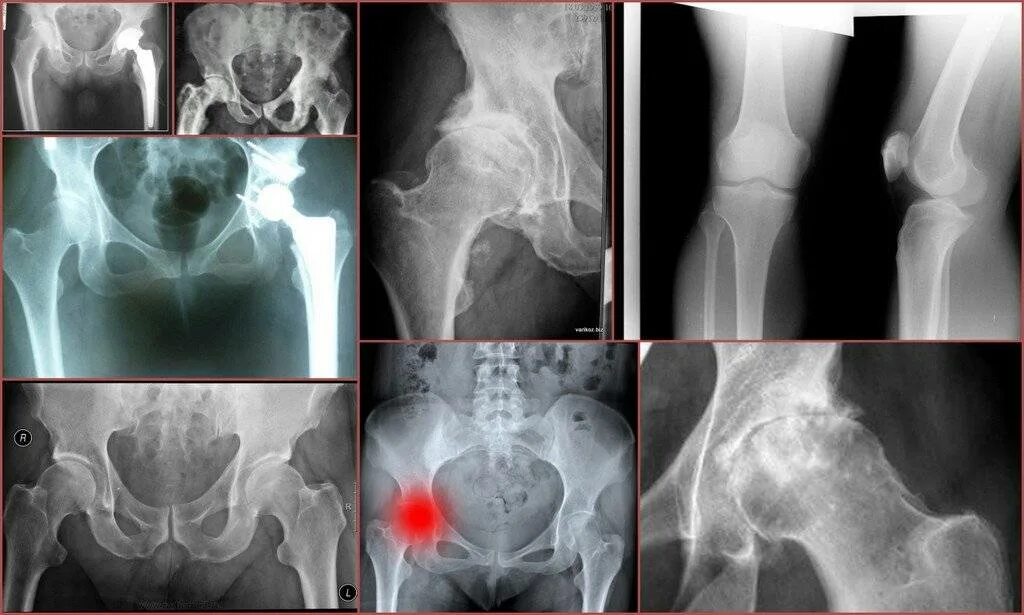

Можно ли лечить тазобедренный сустав